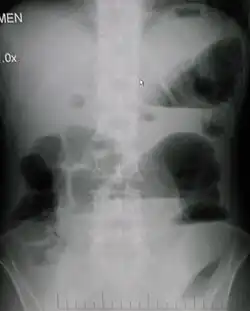

Upright abdominal X-ray demonstrating a small bowel obstruction. Note multiple air fluid levels. | |

Radiological signs of bowel obstruction include bowel distension (small bowel loops dilated >3 cm) and the presence of multiple (more than 2) air-fluid levels on supine and erect abdominal radiographs.[16] Ultrasounds may be as useful as CT scanning to make the diagnosis.[17]